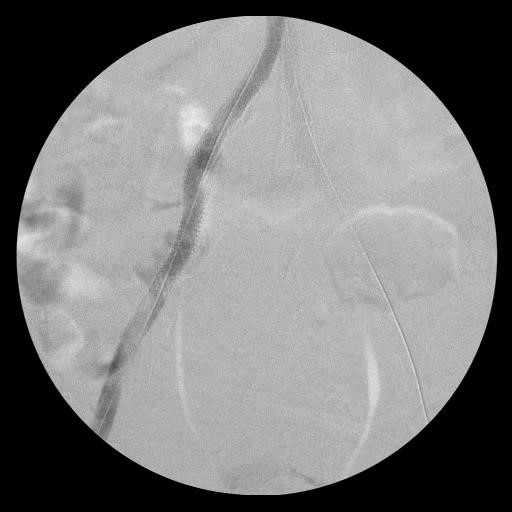

Непосредственный результат.

ЛПИ: 0,8/0,8